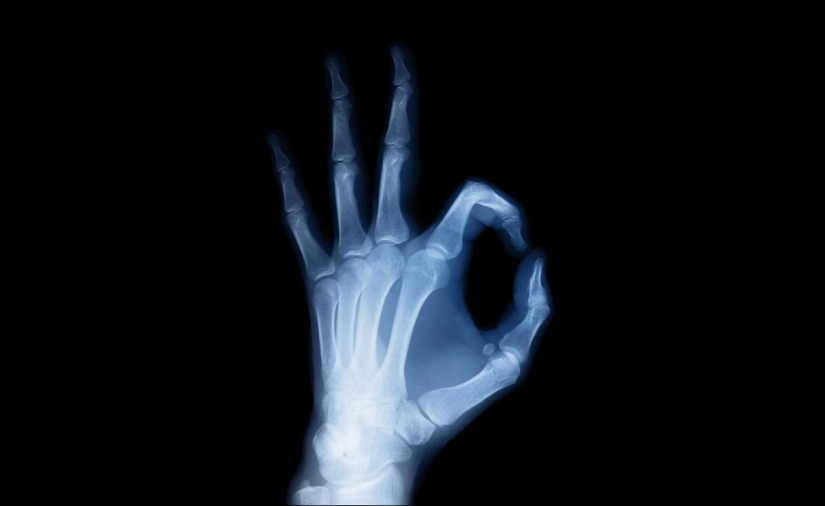

Out of curiosity, in 1895, Wilhelm Roentgen placed his hand in front of a cathode ray tube and saw its image on a photographic plate, allowing him to examine almost every bone. This is how Wilhelm Roentgen discovered the method of the same name.